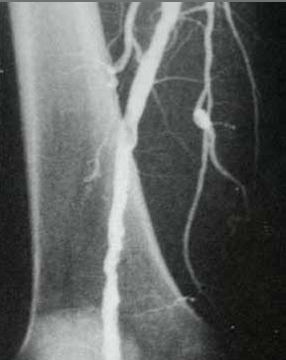

... nach Wiedereröffnung (Dilatation)